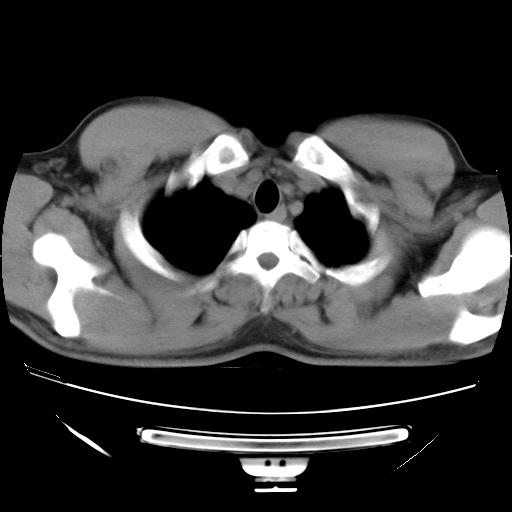

男,38岁,于2009年8月9日晚突发左侧胸痛,今x线提示左下肺阴影,为了明显确诊断,行ct检查,

血常规:嗜酸性细胞增高,单核细胞增高。

纵膈窗